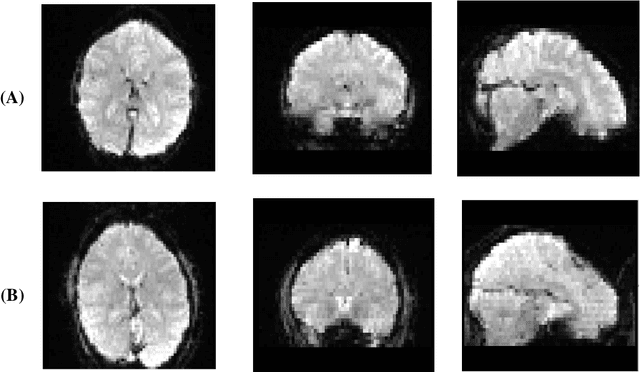

Abstract:Nowadays, many people worldwide suffer from brain disorders, and their health is in danger. So far, numerous methods have been proposed for the diagnosis of Schizophrenia (SZ) and attention deficit hyperactivity disorder (ADHD), among which functional magnetic resonance imaging (fMRI) modalities are known as a popular method among physicians. This paper presents an SZ and ADHD intelligent detection method of resting-state fMRI (rs-fMRI) modality using a new deep learning (DL) method. The University of California Los Angeles (UCLA) dataset, which contains the rs-fMRI modalities of SZ and ADHD patients, has been used for experiments. The FMRIB software library (FSL) toolbox first performed preprocessing on rs-fMRI data. Then, a convolutional Autoencoder (CNN-AE) model with the proposed number of layers is used to extract features from rs-fMRI data. In the classification step, a new fuzzy method called interval type-2 fuzzy regression (IT2FR) is introduced and then optimized by genetic algorithm (GA), particle swarm optimization (PSO), and gray wolf optimization (GWO) techniques. Also, the results of IT2FR methods are compared with multilayer perceptron (MLP), k-nearest neighbors (KNN), support vector machine (SVM), random forest (RF), decision tree (DT), and adaptive neuro-fuzzy inference system (ANFIS) methods. The experiment results show that the IT2FR method with the GWO optimization algorithm has achieved satisfactory results compared to other classifier methods. Finally, the proposed classification technique was able to provide 72.71% accuracy.